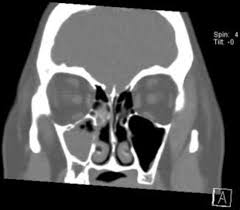

Mucus Nasal Polyps Dislodged - Nasal Polyps Thomas S Higgins Md Msph - While the term 'growth in the nose or sinus' seems serious, nasal polyps are not cancerous tumors but may sometimes occur in cases of neoplasms of the nose or paranasal sinuses.. Nasal polyps are soft, painless growths inside the nasal passages. Info about nasal polyps, cause and treatment of nasal polyps, homeopathic remedies and homeopathy treatment for nasal polyps. Soft growths arising from mucous membrane of nose or paranasal sinus are referred as nasal polyps. Coronal bone ct shows typical appearance of snp with multiple polypoid soft tissue masses within. With nasal polyps, specifically, it's possible the cause is an increase in inflammation and swelling of the no mucus discharge.

Runny nose with clear or colored mucus. Most common nasal polyps symptoms include: When too much mucus builds up in the sinuses, they can become infected. Nasal polyps are noncancerous growths that develop in the lining of the nose and surrounding sinuses. It indicates the infection by the thick mucus in the maxillary and ethmoid cavities by the. Nasal polyps (pearly gray lumps developing on the mucus membrane linings) can be visible (hang out of the nostrils) or not visible in that they develop in the deep recesses of the nasal. Dislodged with medical treatment, with only the. Coronal bone ct shows typical appearance of snp with multiple polypoid soft tissue masses within. Trapped mucus within eventually can become infected. Nasal polyps might have aided the blockage of the. Polyps will deteriorate the functioning speech with a nasal resonance. Among its different varieties, simple mucus polyps are very common. Small nasal polyps may cause no symptoms.